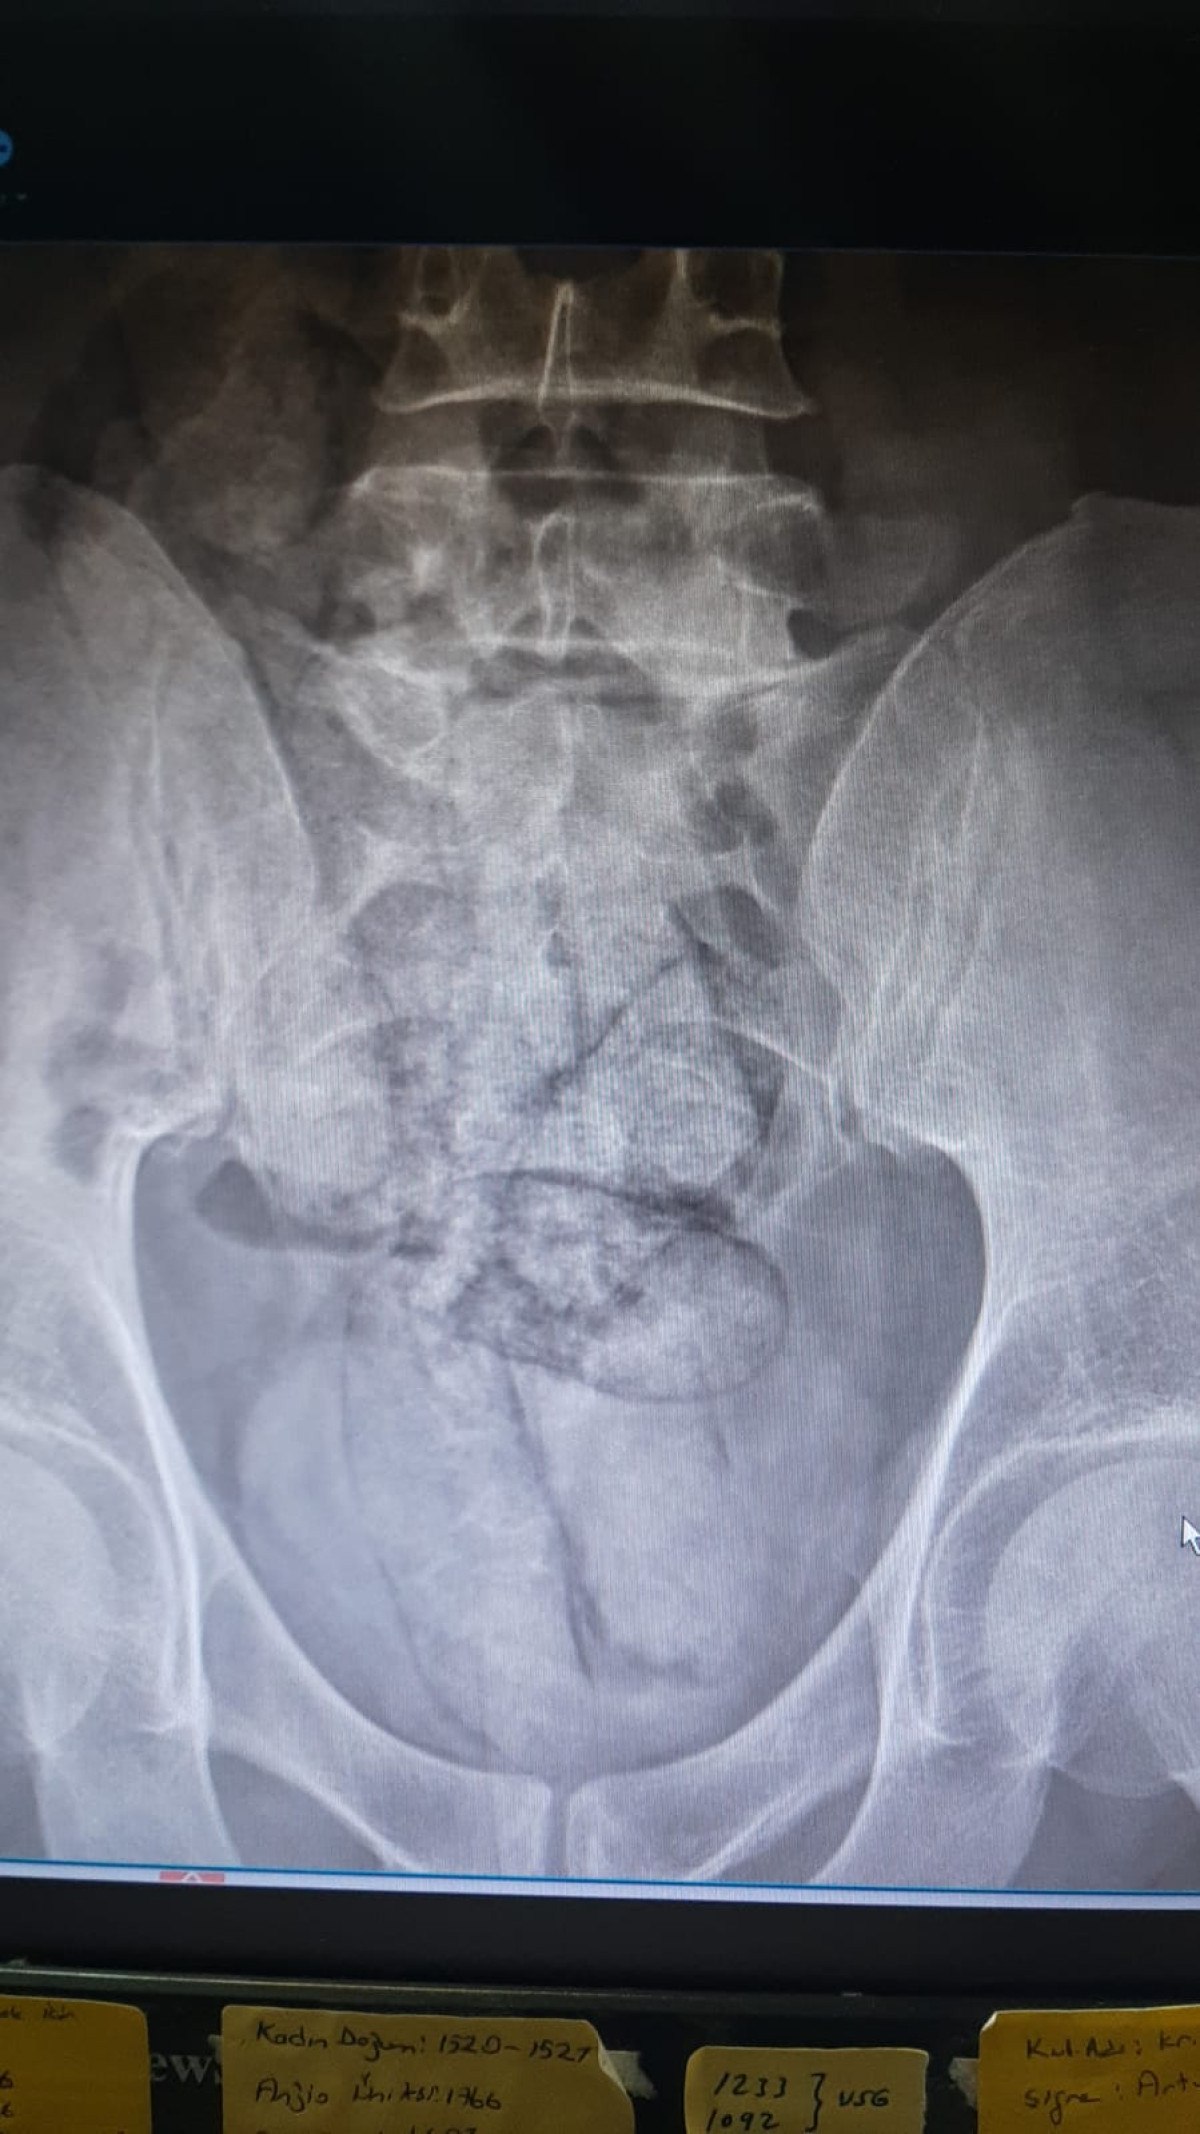

Artvin Devlet Hastanesi’ne götürülen F.R.’nin yapılan tomografisinde, bağırsaklarında 10 paket uyuşturucu madde taşıdığı belirlendi.

Şüphelinin hayati tehlike oluşturabilecek şekilde sakladığı paketler cerrahi müdahale ile çıkarıldı.